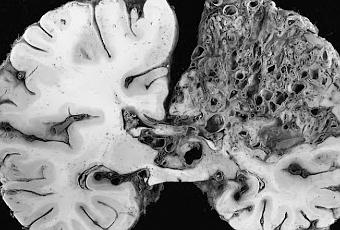

Malformation artério-veineuse cérébrale.

Source iconographique et légendaire: http://fr.wikipedia.org/wiki/Malformation_art%C3%A9rio-veineuse_c%C3%A9r%C3%A9brale